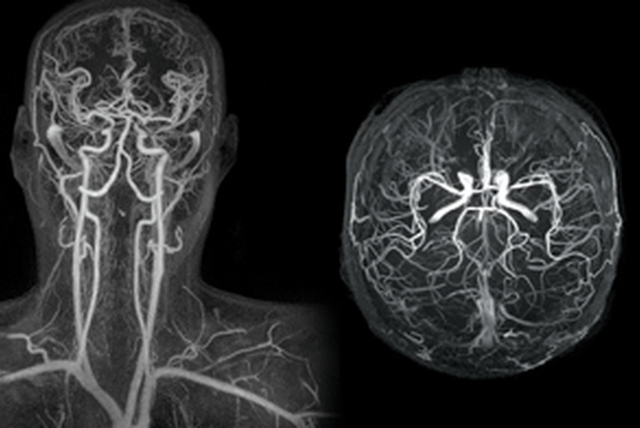

Μαγνητική Αγγειογραφία (MRA)

Η Μαγνητική Αγγειογραφία (MRA) είναι μια μη επεμβατική εξέταση που χρησιμοποιεί τη μαγνητική τεχνολογία και τους υπολογιστές για να δημιουργήσει λεπτομερείς εικόνες των αγγείων στο εσωτερικό του σώματος, συμπεριλαμβανομένων των αρτηριών και των φλεβών. Η MRA χρησιμοποιεί το μαγνητικό πεδίο και ραδιοκύματα για τη δημιουργία λεπτομερών εικόνων των αγγείων, χωρίς τη χρήση ακτινοβολίας.

Υπάρχουν διάφοροι τύποι MRA, και ορισμένοι από τους συνηθέστερα χρησιμοποιούμενους περιλαμβάνουν:

Time-of-Flight MRA (TOF-MRA): Αυτή η μέθοδος εκμεταλλεύεται τη διαφορά στη ροή του αίματος για να δημιουργήσει εικόνες των αγγείων. Είναι ευαίσθητη στη ροή του αίματος και συνήθως χρησιμοποιείται για την αξιολόγηση των αρτηριών.

Contrast-Enhanced MRA (CE-MRA): Σε αυτήν τη μέθοδο, ενέσεις με χρωστικές ουσίες που είναι ορατές στις εικόνες μαγνητικής αγγειογραφίας εισέρχονται στην κυκλοφορία του αίματος για να προσδώσουν αντίθεση στις εικόνες. Αυτή η μέθοδος παρέχει πιο λεπτομερείς εικόνες των αγγείων και είναι ευαίσθητη στη ροή του αίματος.

Η MRA χρησιμοποιείται συχνά για την αξιολόγηση των αγγείων σε διάφορα μέρη του σώματος, συμπεριλαμβανομένων των καρωτίδων, της κοιλιακής αορτής, των εγκεφαλικών αγγείων και άλλων περιοχών. Είναι χρήσιμη για την ανίχνευση στενώσεων, ανευρυσμάτων, ή άλλων ανωμαλιών στο σύστημα κυκλοφορίας του αίματος.